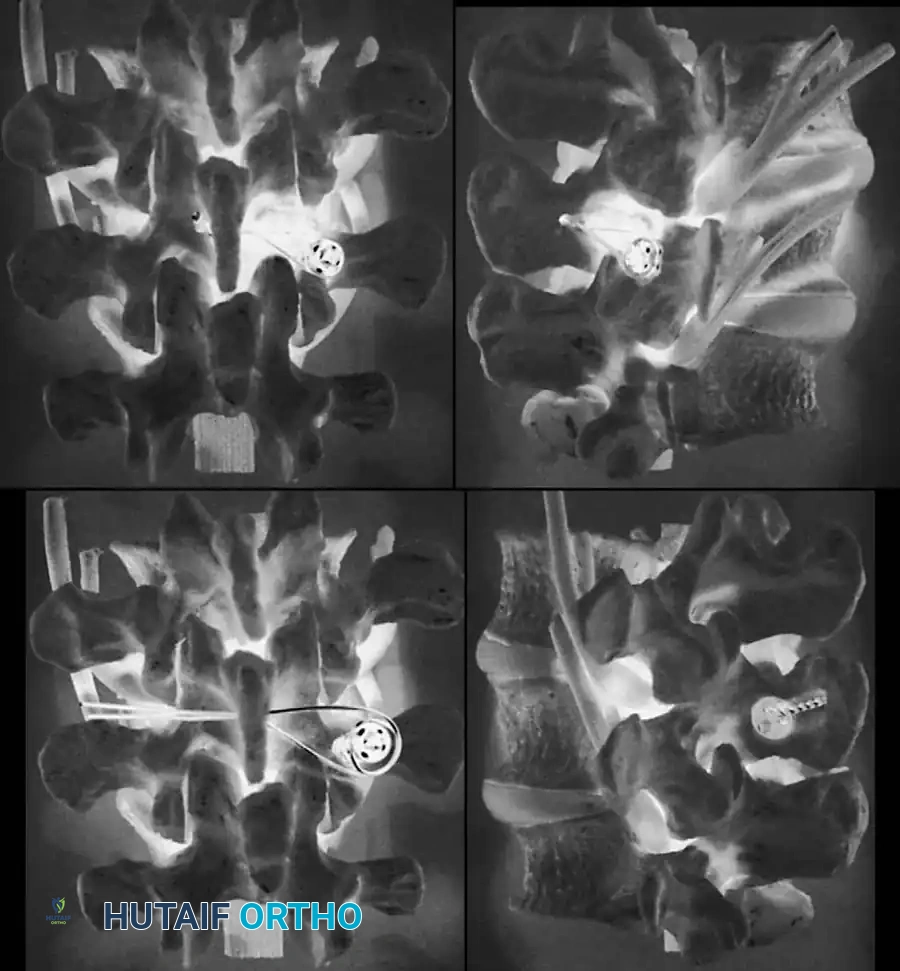

- Ferguson Coronal View: The X-ray beam is angled 30 degrees cephalad (parallel to the L5-S1 disc space). This provides a true en face view of the L5 pedicles, transverse processes, and sacral ala.

- Oblique Views: Historically used to visualize the "Scottie Dog" collar (pars defect), though largely superseded by advanced imaging for subtle lesions.

- Computed Tomography (CT): The gold standard for defining osseous anatomy, confirming acute stress fractures versus chronic non-unions with sclerotic margins, and planning pedicle screw trajectories.

A standard posterior midline incision is utilized. Subperiosteal dissection exposes the spinous processes, laminae, pars interarticularis, and transverse processes of L4, L5, and the sacral ala.

Surgical Pitfall: In severe dysplastic slips, the anatomy is grossly distorted. The L5 lamina

Associated Surgical & Radiographic Imaging